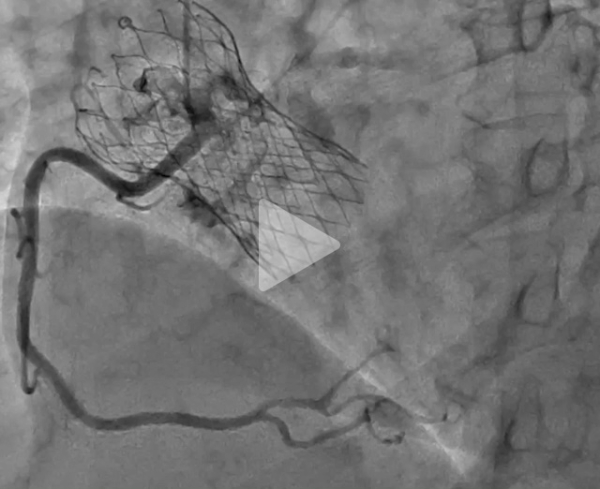

Coronarographie

Vidéo 3 : visualisation non sélective du TCG en cathétérisant la coronaire droite

Vidéo 4 : visualisation du TCG après injection à haute pression du sinus droit